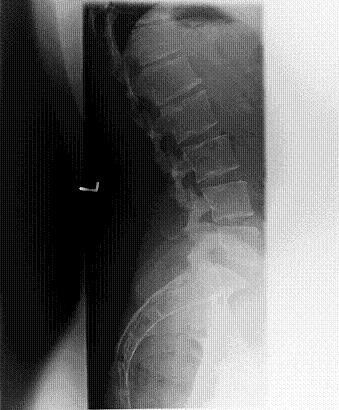

Hallo zusammen...ich bin Melissa, 28 aus dem schönen Emsland. Ich habe seit langer Zeit Probleme mit dem Rücken. Sprich LWS sowie HWS. Ich habe im Lendenwirbelbereich starke Schmerzen, die mittlerweile bis ins rechte Bein ausstrahlt. Dazu habe ich starke Nacken und Kopfschmerzen und Kribbeln in der rechten Hand. Ich habe immer wieder KG und Massagen bekommen. Das brachte aber nur für den Moment Linderung. Dort wurde mir vom Therapeuten geraten, mal ein Röntgenbild machen zu lassen. Termin beim Orthopäden, Gespräch und dann ab zum Röntgen. Der Orthopäde ist, muss ich dazu sagen, sehr "sonderbar", hat immer stumpfe Sprüche auf Lager. Leider gibt es hier oben nicht eine große Auswahl an Fachärzten. Er erkannte dann wohl auf den Röntgenbildern, dass ich am Morbus Scheuermann leide und verkrümmungen der Wirbelkörper und der unteren LWS habe. Auch das Bild der HWS war wohl nicht ganz okay und er meinte es seinen 3 Bandscheiben schon "extrem dünn" und auf Dauer könne man einen Vorfall nicht verhindern. Er veranlasste kein MRT und meinte nur : "Tja ich kann ihnen ja kaum eine neue WS einsetzen."

So nun war gestern endlich mein MRT Termin. Sitze nun schon den ganzen Morgen vorm PC und durchstöbere das Netz um Bilder zu vergleichen. Leider habe ich null Ahnung wie es da aussieht, ob dass alles so sein muss etc. Irgendwie bin ich dann auf dieses Forum gestoßen. Ich lade euch jetzt erstmal ein paar Aufnahmen hoch. Vlt könnt ihr ja was drauf erkennen

Auf dem Röntgenbild der LWS kann man erkennen, dass Deine Bandscheiben in der unteren BWS bzw. im Übergang BWS/LWS offensichtlich nicht mehr so hoch sind, wie sie eigentlich sein sollten. Ein deutliches Zeichen für eine Überlastung bzw. Degeneration der Bandscheiben. Du sagst, dass Du im Gartenbau arbeitest, was das auch ein Stück weit erklären könnte. Denn Du arbeitest offensichtlich körperlich und nicht am Schreibtisch.

Generell gilt aber auch hier: die Bilder sind zu klein, um sie objektiv beurteilen zu können. Dies geht nur "live", am besten mit den Rö-Folien in der Hand.